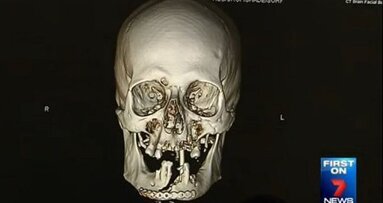

In maart 2014 schoot Stubblefield zichzelf thuis in Mississippi in de badkamer neer. De kogel, die haar mond en neusholte doorboorde, zorgde voor onherstelbare beschadigingen aan meerdere botten in haar gezicht en kaak, en beschadigde haar ogen ernstig. Voor aanvang van de volledige gezichtstransplantatie onderging ze 22 operaties die gericht waren op functieherstel. Toch had ze nog steeds regelmatig moeite met simpele dingen zoals eten.

Nadat ze in november 2015 de instemmingsformulieren voor de gezichtstransplantatie had ondertekend, duurde het nog 18 maanden voordat Stubblefield de operatie onderging. Tijdens de operatie verving een team van 11 chirurgen al haar gezichtsweefsel met dat van de donor. Daarnaast zijn Stubblefields bovenkaak en twee derde van haar onderkaak vervangen met bot van de donor.